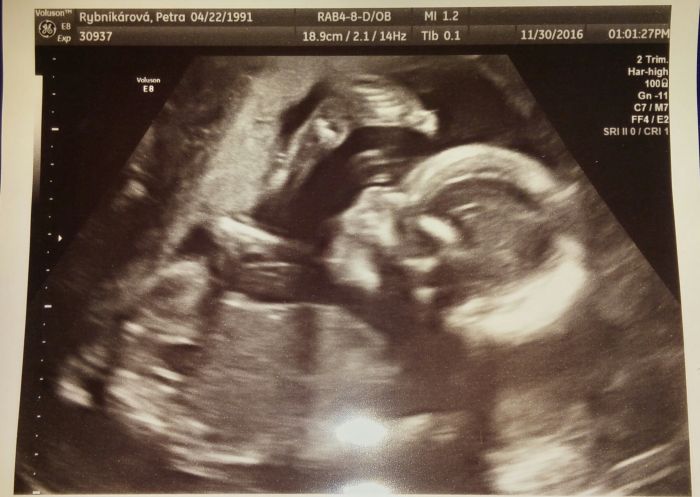

Ahojte, tak máme screening za sebou. Všechno v pořádku, mimi má 379g a je to chlapeček :)) Bude nejspíše Adámek :) Jsme moc rádi, po 4 neteřích aspoň změna :D

a tady ještě fotečka našeho prcka :))